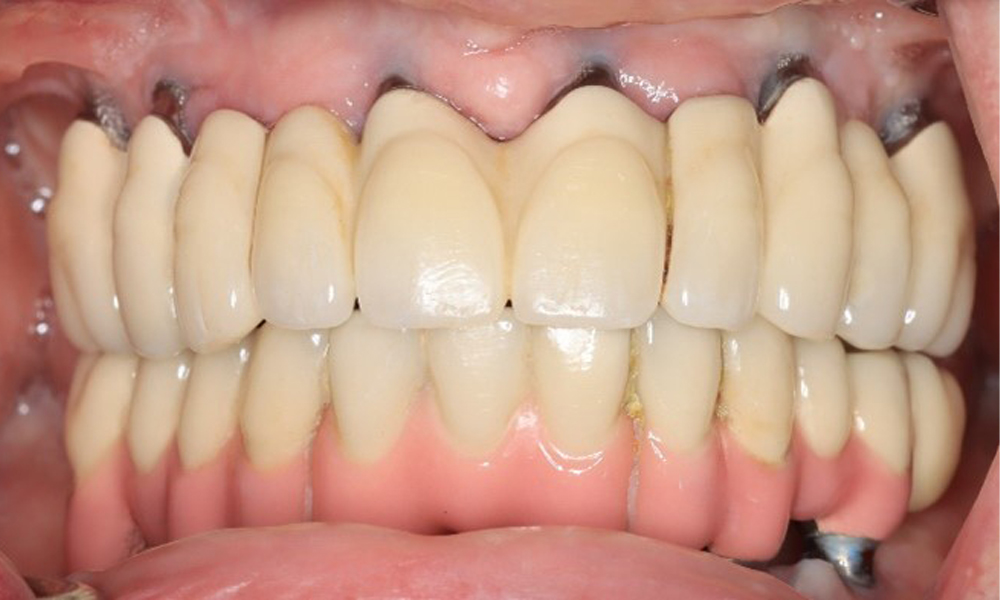

Eine 74-jährige Patientin stellt sich in der Sprechstunde vor. Die Anamnese zeigt, dass die Patientin gut eingestellten Bluthochdruck hat und Lixiana einnimmt. Weiterhin hatte die Patientin im Jahr 2020 ein Nierenkarzinom. Die Lebensgewohnheiten der Patientin sind unauffällig. Die Patientin hat keine eigenen Zähne mehr. Sie hat im Oberkiefer und Unterkiefer jeweils sechs Implantate, die mit Kronen bzw. über Brücken versorgt sind. Anhand der aktuellen Befunde lässt sich keine periimplantäre Mukositis bzw. Periimplantitis feststellen; vereinzelte (geringfügige) Blutungen an den Implantat(-versorgungen) liegen vor.

Versorgungen: Implantate regio 011, 013, 015, 021, 023, 025, 031, 033, 035, 042, 044, 046

Die periimplantäre Situation ist derzeit stabil. Aufgrund der Komplexität der Suprakonstruktionen hat die Patientin ein moderates Entstehungsrisiko und ein geringes Progressionsrisiko für periimplantäre Erkrankungen.